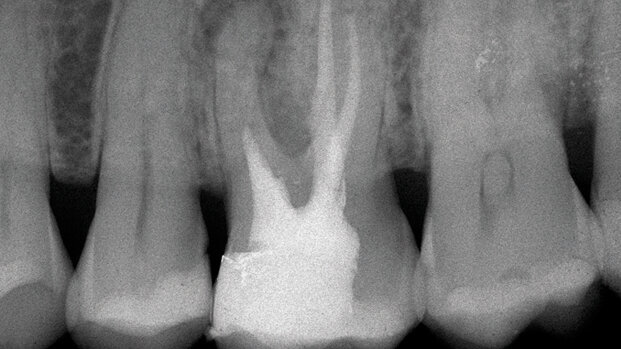

Per endodonzia chirurgica si intende quella branca dell’odontoiatria che si occupa della diagnosi e del trattamento delle lesioni di origine endodontica che non rispondono alla terapia endodontica convenzionale o che non possono essere trattate con la terapia endodontica convenzionale.

Lo scopo dell’endodonzia chirurgica, pertanto, è quello di ottenere detersione, sagomatura e otturazione tridimensionale della porzione apicale del sistema dei canali radicolari non trattabili attraverso la cavità d’accesso, ma raggiungibili solo attraverso un lembo chirurgico. Per questo motivo si preferisce utilizzare il termine “endodonzia chirurgica” anziché “chirurgia endodontica”, in quanto l’intervento deve essere programmato ed eseguito come un intervento di endodonzia fatto attraverso un accesso chirurgico, e non solo come un intervento di chirurgia fatto per motivi endodontici.

Una volta che è stata fatta la diagnosi di insuccesso endodontico, è necessario capire quali sono state le cause che hanno portato all’insuccesso stesso, per valutare successivamente se esista la possibilità di correggere il fallimento con un ritrattamento ortogrado. Solo nel caso in cui questa possibilità non esista o, meglio, solo dopo che i tentativi di risolvere la terapia per via non chirurgica siano falliti, siamo autorizzati a intervenire per via chirurgica. L’endodonzia chirurgica, in altre parole, non è il sostituto di un’endodonzia approssimativa e non deve essere una scappatoia per lasciare non “ritrattata” una terapia endodontica ortograda inadeguata.

In accordo con quanto affermato da Nygaard-Ostby e Schilder8, l’endodonzia chirurgica deve essere riservata a quei casi nei quali la preparazione e l’otturazione dei canali radicolari appaiono impossibili fin dall’inizio, o quando i tentativi di ritrattamento non chirurgico siano falliti. Anche in questi casi, tuttavia, gli autori raccomandano di riempire con le metodiche tradizionali la maggior parte possibile di canale prima di procedere all’intervento chirurgico.